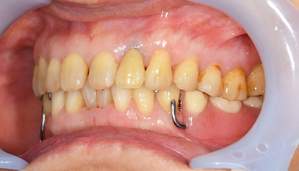

左の写真は歯が歯肉縁上にないのがわかります。右では歯肉縁上に1周にわたって歯牙があるのがわかります。

レントゲンで見ても、右上2では歯質が歯肉縁上にのこっていない。しかし歯根は長いのでMTMの適応症例です。

歯を挺出しているところ。